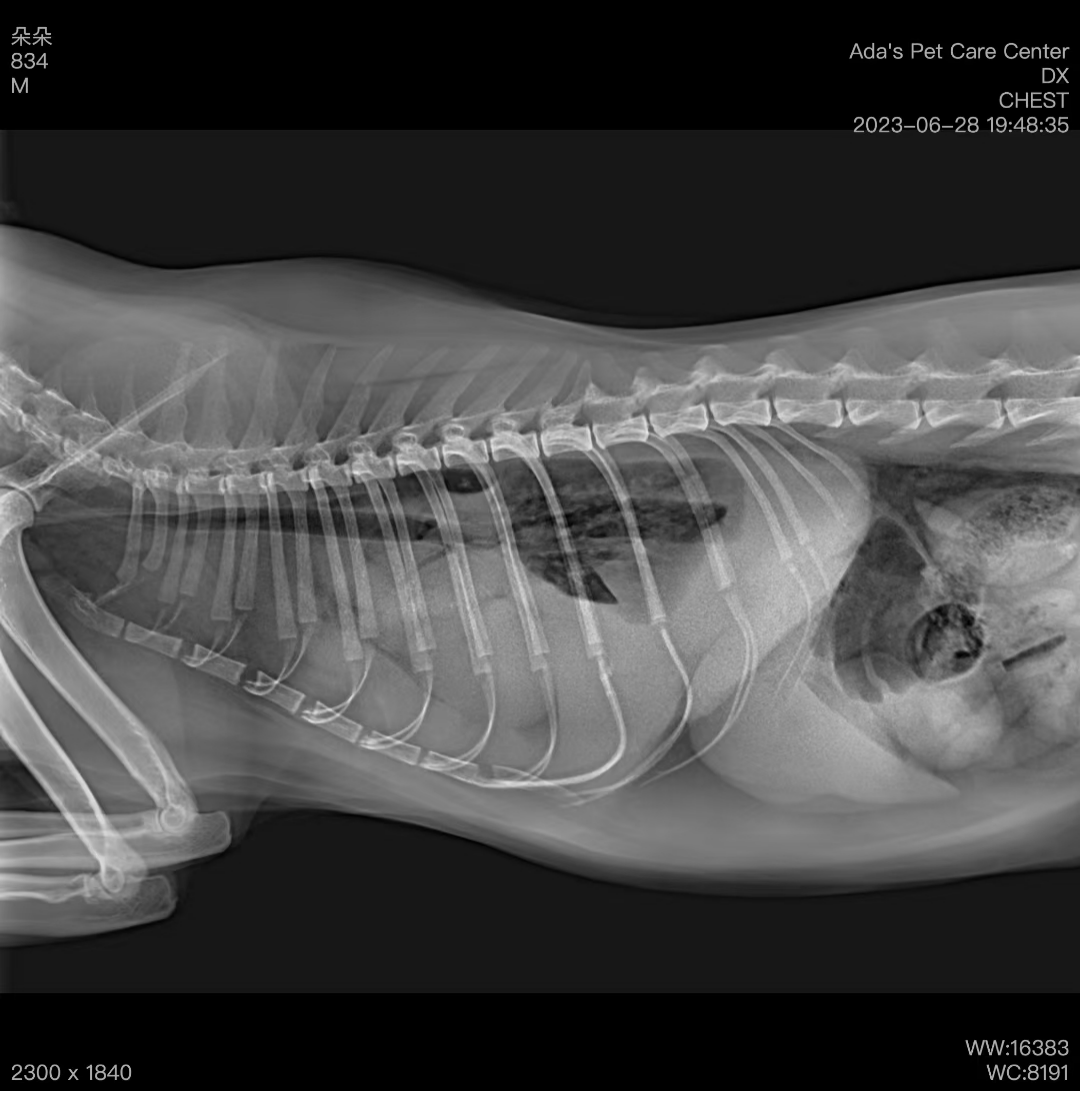

📌 基本信息🔍 诊断与病情分析本院在为该猫咪进行体检时,发现其胸部X光片显示心脏轮廓异常。进一步进行心脏超声及腹部超声检查后,确诊为心包横膈疝。该病属于较为罕见的先天性畸形,部分病例可能长期无症状,但若腹腔脏器进入心包腔并产生压迫,可能会影响心脏功能,甚至…

最近,我们诊所接诊了一只急诊宠物——Nana,它突然出现了呼吸急促、活动耐受性差和精神萎靡等症状。这些表现明显不太像普通的小病,于是我们马上进行了详细的检查。初步检查和诊断结果首先,我们进行了胸部X光检查,发现肺部出现弥漫性密度增高的现象,这可能是肺部积水的信号…